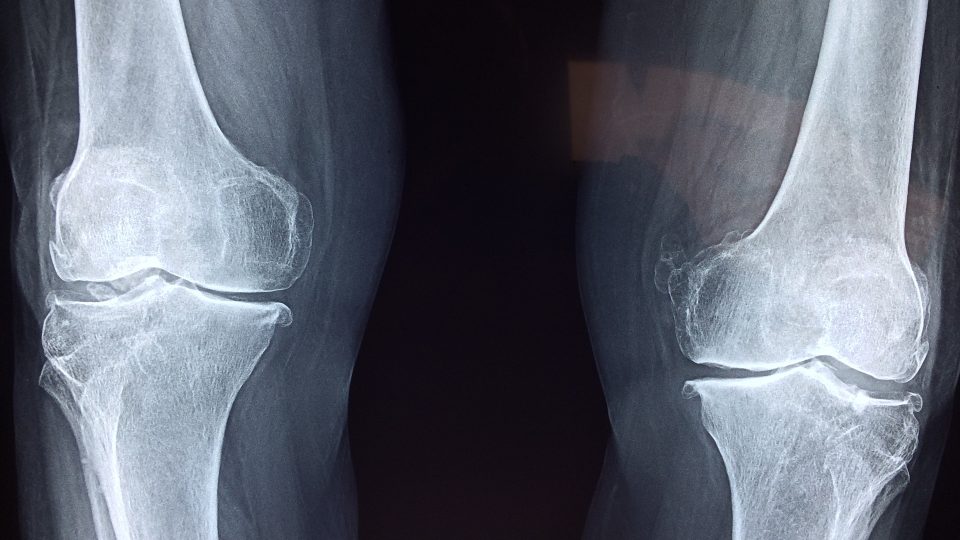

Hořčík patří mezi prvky, které pro chod organismu nezbytně potřebujeme. Velké množství ho přitom máme v kostech. Posluchačku zajímá, jestli užívání potravinových doplňků s hořčíkem může bránit vzniku zlomenin v důsledku osteoporózy. Vědci se touto problematikou už intenzivně zabývají.

Jelikož osteoporóza představuje závažný zdravotní problém hlavně pro mnoho seniorů, lékařský výzkum intenzivně zkoumá faktory, které k němu přispívají, i cesty, jak mu předcházet. Vyhodnocení dostupných studií ukazuje, že příjem hořčíku by mohl souviset s mírou mineralizace kostní tkáně. Například velká americká studie, která byla zveřejněna v roce 2014, sledovala více než 70 tisíc žen v menopauze a ukázala, že ženy s nižší mineralizací kyčle a dalších kostí vykazovaly nižší příjem hořčíku v potravě. Nicméně studie nenalezla rozdíl v riziku vzniku zlomeniny mezi skupinami žen s různým příjmem hořčíku.

V roce 2016 bylo zveřejněno vyhodnocení 24 tzv. observačních studií, které po dlouhou dobu sledovaly životní styl velkých skupin lidí a jeho dopad na zdraví. Výsledky hodnocení ale nenašly souvislost mezi vyšším příjmem hořčíku a rizikem zlomeniny krčku kyčelní kosti, ani celkovým rizikem vzniku zlomeniny. Existují také klinické studie, které testují, jestli se podaří podáváním doplňků stravy s obsahem hořčíku zvýšit mineralizaci kostí. Výsledky ale zatím nejsou jednoznačné. V současné době tedy není jasné, zda by vůbec podávání takových doplňků mohlo snížit riziko vzniku zlomeniny, a případně jaké množství hořčíku by bylo nutné užívat.